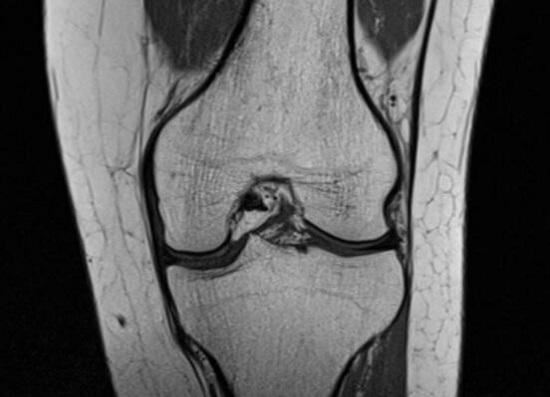

膝关节慢性病变;的症状往往是这样的:没有缘由的膝关节疼痛、上下楼梯过程中的膝关节前侧疼痛、受凉或潮湿环境中的隐痛、关节内部出现绞锁和卡顿等。膝关节慢性病变引发的疼痛往往位于膝关节深处,用手指按压难以找到明确的痛点,通过细致的影像学检查(例如:核磁)能够发现轻微的物理损伤。